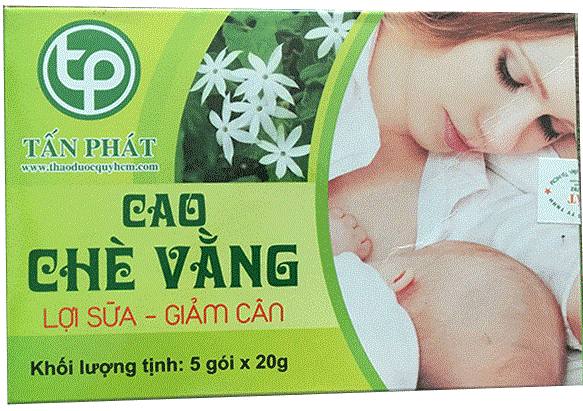

Cao Chè Vằng

Cao chè vằng có thực sự tốt cho phụ...

Dưỡng chất Glycosat có trong chè vằng có tác dụng kích thích ăn ngon, tiêu...

Cách sử dụng cao chè vằng đúng cách

Cách uống cao chè vằng đúng cách Chè vằng từ lâu đã được biết đến...

Cao chè vằng có tác dụng gì cho sức...

Cao chè vằng được chiết suất từ thân và lá cây Vằng Sẻ. Vậy cao chè...